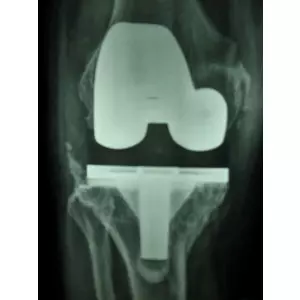

Ratibhai Patel

hip replacement surgery

Ratibhai Patel Details